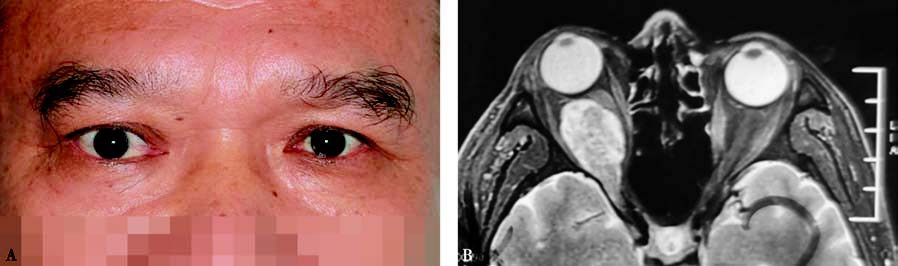

Figure 1 External appearance and imaging of a patient with orbital schwannoma in the right eye

A. External appearance shows proptosis of the right eye.

B. Axial T1-weighted MRI with contrast enhancement shows inhomogeneous enhancement of the tumor with invasion into the superior orbital fissure.